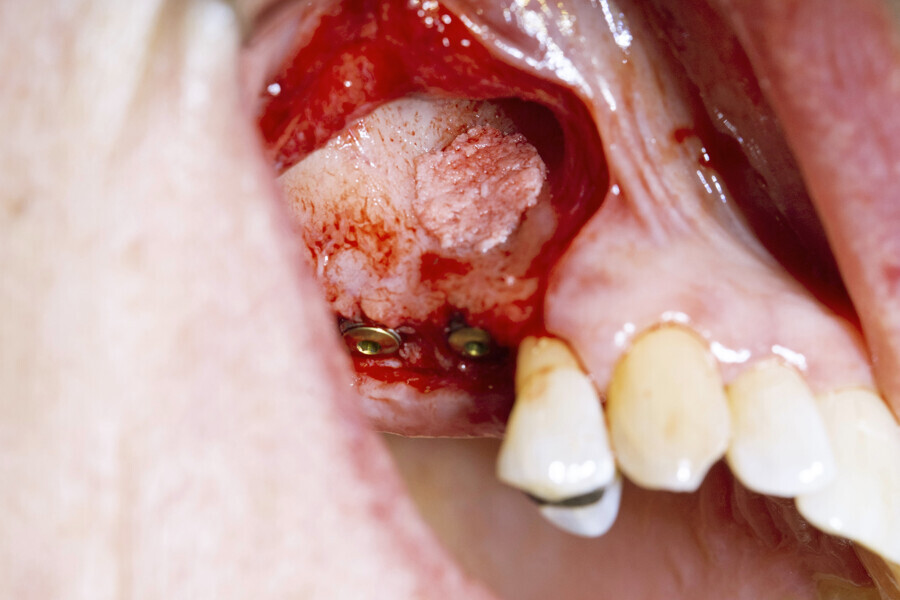

Next, the large quantity of autogenous bone collected with the disposable BoneTrap (Dentsply Sirona) during surgery was used to augment the small bone fenestration (Figs. 6 & 7), and Symbios Xenograft Granules were layered over the autogenous bone (Fig. 8). Finally, Symbios Collagen Membrane SR (15 × 20 mm) was trimmed to shape to complete the guided bone regeneration procedure (Fig. 9). The wound was closed with PGA sutures (Fig. 10), and radiographic evaluation was performed to verify the implants postoperatively (Fig. 11). Three months later, medium Healing Abutments EV were placed (Fig. 12).

Fig. 6: Use of the BoneTrap to augment the small bone fenestration.

Fig. 7: Large quantity of autogenous bone collected from the BoneTrap.